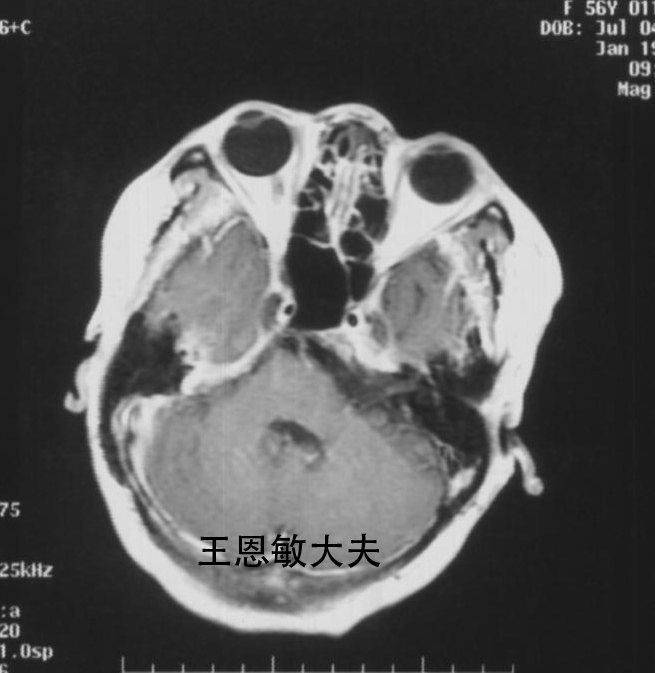

复发听神经瘤的射波刀治疗--每周一例